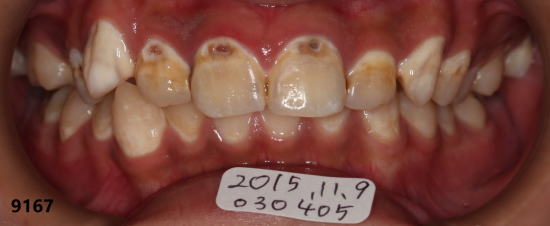

| 初診時の口腔内写真:2015年08月26日 砂糖が入ったスポーツドリンクの常用で全体の歯がむし歯になりかけ 砂糖入りのスポーツドリンクをやめて、毎日フッ素洗口をするよう勧める。 |

前歯の拡大: 矢印の所がむし歯(白濁)が進行している。 |